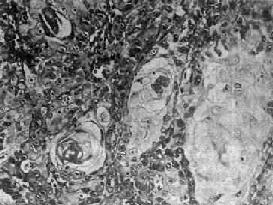

图9-5 鼻咽低分化腺癌 癌巢不规则,部分出现腺腔结构(箭头),癌细胞稍小,核卵圆或圆形,可见核仁 (3)泡状核细胞癌:癌巢不规则,境界不甚明显,癌细胞胞浆丰富,境界不清晰,往往呈合体状聚集成堆。核大呈空泡状,圆形或卵圆形,有1~2个肥大的核仁,核分裂像并不多见(图9-6)。癌细胞间常可见淋巴细胞浸润。电镜下,可观察到紧挨淋巴细胞的癌细胞胞膜和胞质有破坏现象,这可能是淋巴细胞对癌细胞免疫攻击的结果。

图9-6 鼻咽泡状核细胞癌 癌细胞境界不清,呈合体状,核大圆形,染色质少,呈空泡状,含1~2个肥大的核仁,癌细胞间有淋巴细胞浸润 (4)未分化癌:癌细胞小而泡浆少,呈圆形或梭形,核圆形或卵圆形、浓染,细胞呈弥漫浸润,无明显癌巢形成。有时,癌组织主由短梭形细胞组成,颇似燕麦细胞癌(图9-7)。